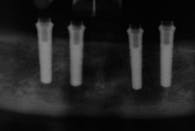

All-on-4 advocates claim that this type of treatment plan reduces cost and saves treatment time, but with the introduction of the ScrewIndirect one-piece implant that provides the implant, abutment, comfort cap, and transfer at a fraction of the cost of the implant alone from all the major implant companies, the economics argument for using the minimum number of implants is no longer valid. The ScrewIndirect screw-receiving platform allows splinting of implants that have up to 40 degree divergence, allowing distal angulations of up to 20 degrees if desired. Placement of five implants in the lower symphysis and six anterior to the maxillary sinuses can be relatively straight and still support adequate length of distal cantilevers. Four ScrewIndirect implants can also be placed, as shown below, splinted with a distal attachment for retention of an overdenture, but providing the patient with a fixed-detachable prosthesis that eliminates the need for a removable prosthesis is a more natural solution to restoring an edentulous jaw.

The ScrewIndirect one-piece implant offers a 3.0 mm D implant with adequate strength. All four diameter options (3.0 mm, 3.7 mm, 4.7 mm and 5.7 mm) have the same 5 mm D multi-unit platform. The 3.0 mm D implant allows treatment of narrow ridges and simplifies accurate placement during flapless surgery. Providing teeth in one day to edentulous patients and immediate implant placement following extractions is becoming the treatment of choice. The patient's existing denture is converted to a fixed-detachable prosthesis immediately following implant placement. This is accomplished by attaching titanium sleeves to the implants that project through holes cut in the denture and attached them to the denture with cold-cure acrylic followed by shortening the denture flanges.